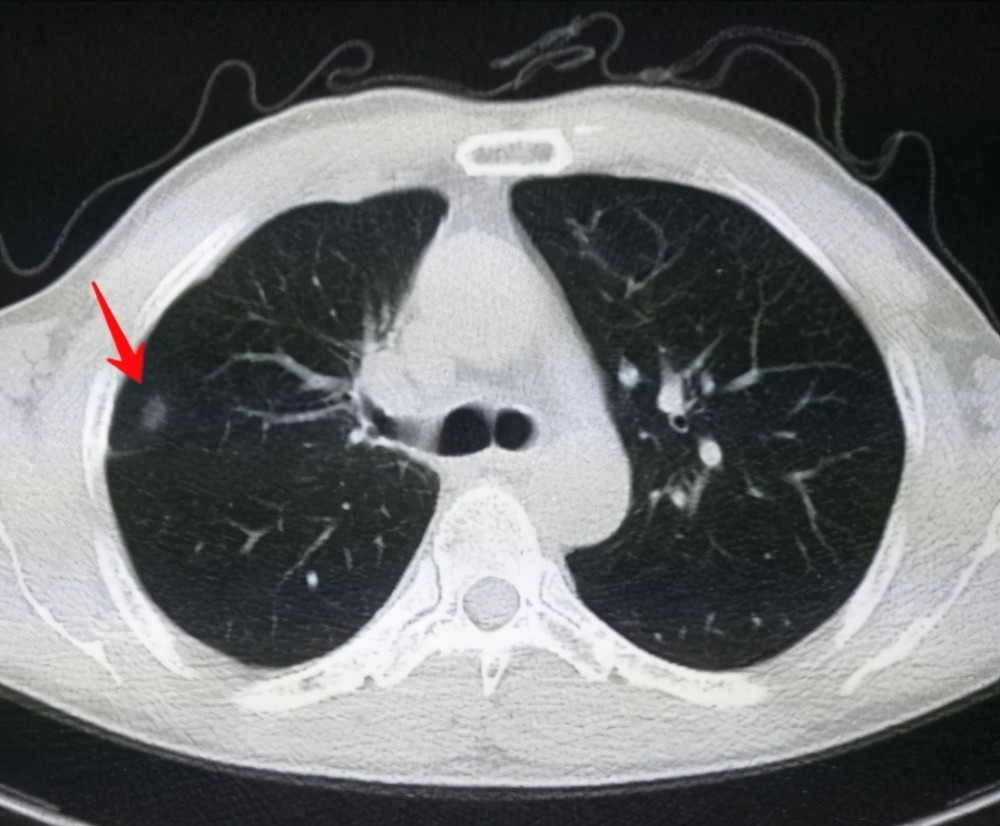

6、定期體檢:定期進行肺部檢查,及時發(fā)現(xiàn)并治療肺結(jié)節(jié)。

對于已經(jīng)發(fā)現(xiàn)肺結(jié)節(jié)的患者,應(yīng)及時就醫(yī),進行進一步的檢查和治療,醫(yī)生會根據(jù)患者的具體情況制定個性化的治療方案,包括藥物治療、手術(shù)治療等,早期發(fā)現(xiàn)、早期治療是提高肺結(jié)節(jié)治愈率的關(guān)鍵。